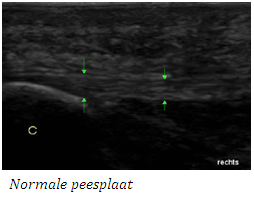

Met een echo kunnen de spieren, pezen, banden, slijmbeurzen, cystes en ganglions in de voeten en knieën in beeld worden gebracht.

Met echografisch onderzoek kunnen we: